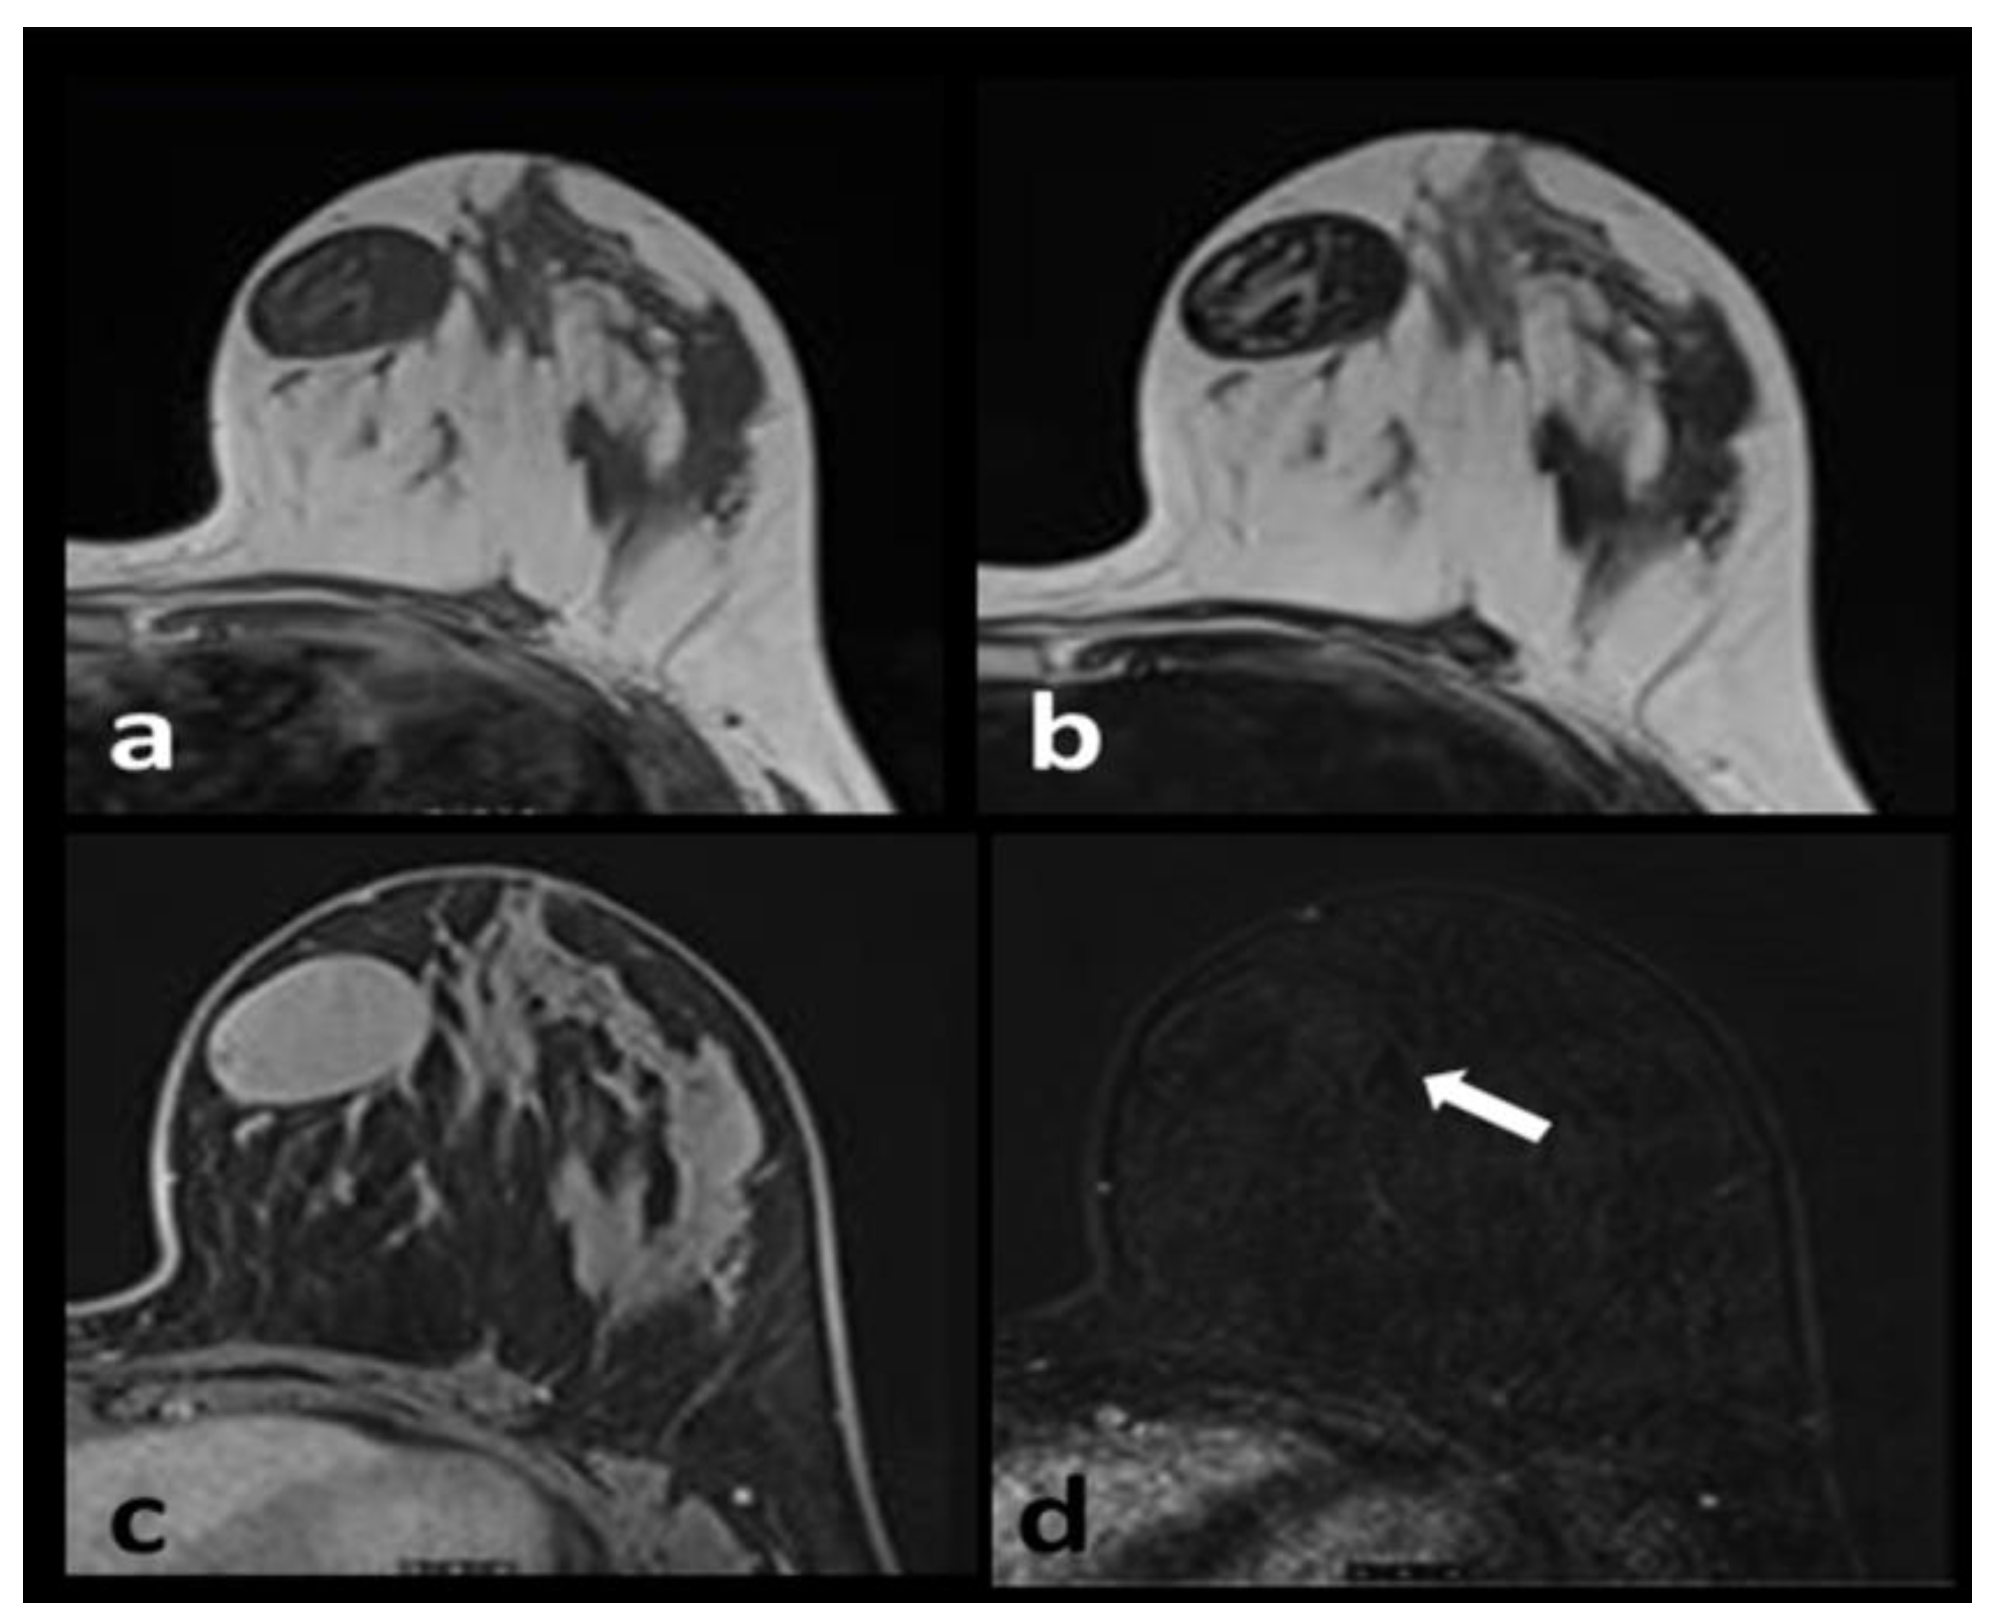

Fibromatosis